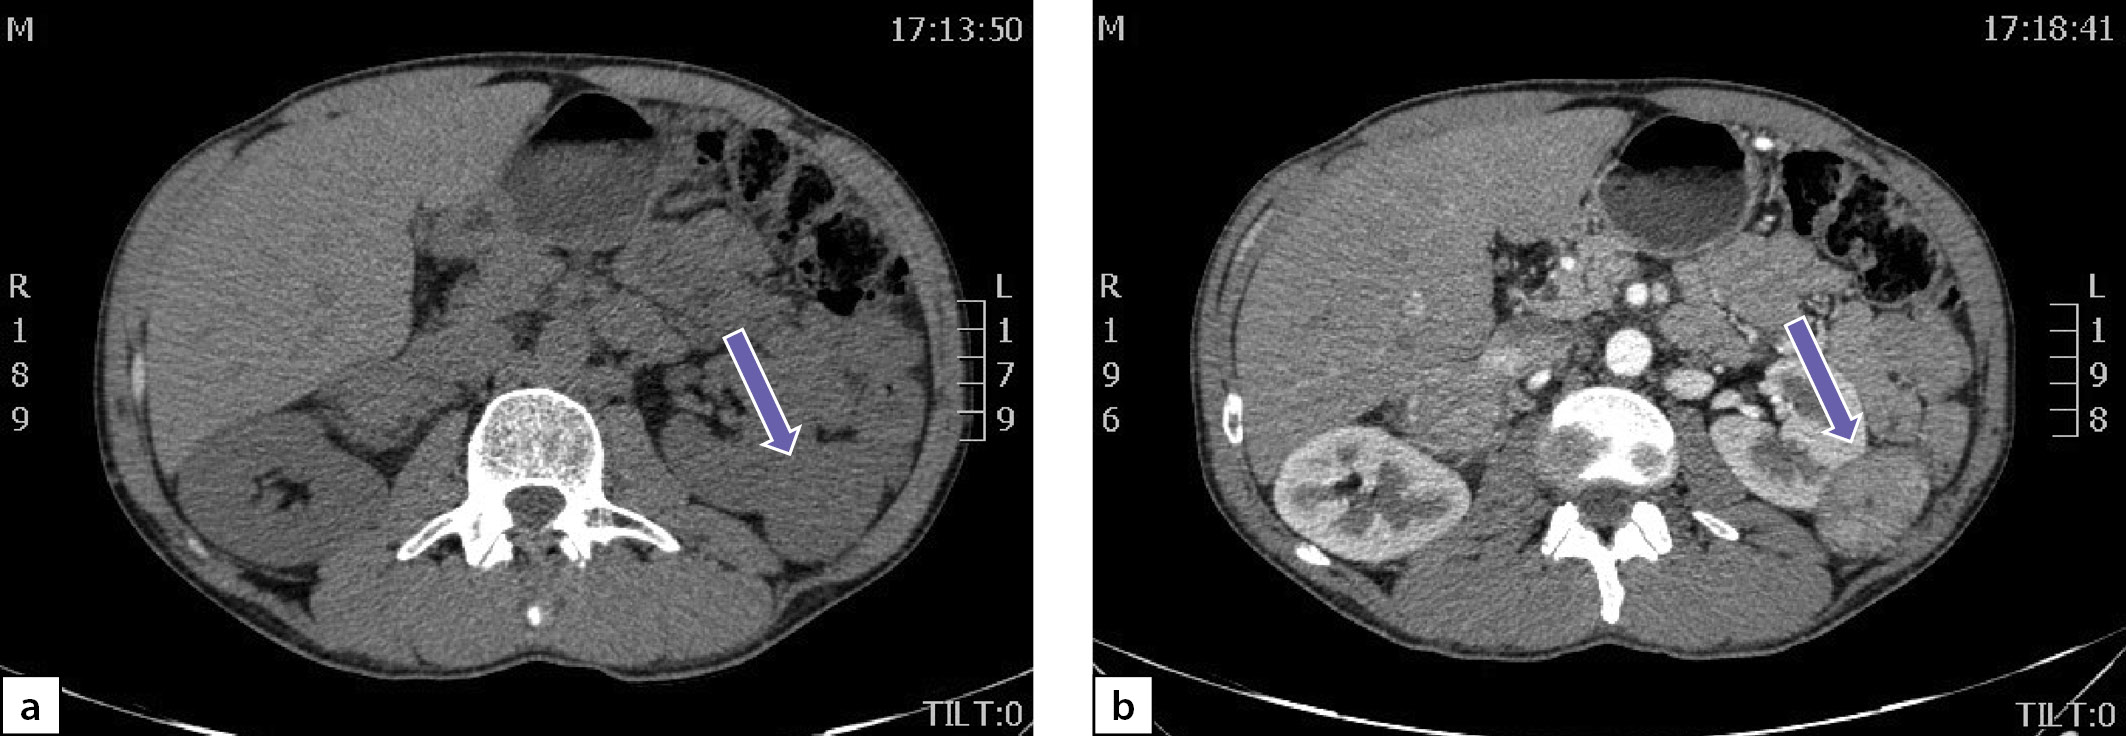

По данным мультиспиральной компьютерной томографии (МСКТ) брюшной полости и забрюшинного пространства с в/в контрастным усилением: в правом надпочечнике, занимая все его пространство, определяется объемное образование с четкими контурами, размерами 80х75х85 мм, плотностью в артериальную фазу 66 НU, в венозную фазу 69 НU, в паренхиматозную фазу 62 НU, в отсроченную до 51 НU (рис. 2 a, b). Кроме того, в забрюшинном пространстве, слева, с деформацией левой почки на уровне средней трети, определяется объемное образование размерами 49х37х47 мм, преимущественно мягкотканой плотности 31 НU, неоднородной структуры, с наличием участков пониженной плотности. Накопление контрастного вещества в артериальную фазу 86 НU, в венозную фазу 112 НU, в паренхиматозную фазу 85 НU, в отсроченную до 62 НU (рис. 3 a, b).

Рисунок 2. Феохромоцитома правого надпочечника:

а) нативная фаза; b) после введения контрастного препарата.

Figure 2. Pheochromocytoma of the right adrenal gland:

a) native phase; b) after administration of a contrast agent.

Учитывая молодой возраст пациента, злокачественный КТ-фенотип выявленных образований и наличие артериальной гипертензии, у пациента были все основания для исключения ФХЦ.